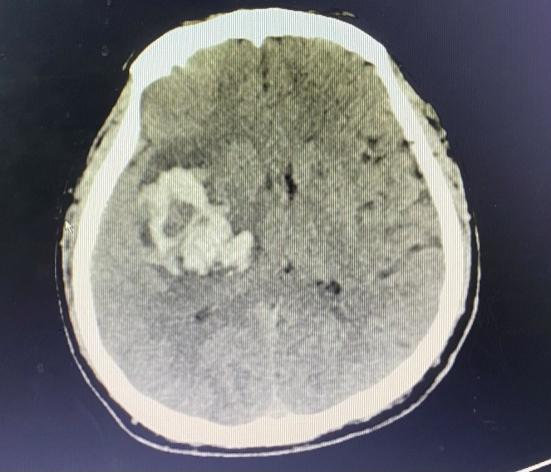

患者黃先生,44歲,4月29日凌晨突感頭痛伴左肢體乏力、言語含糊,被家屬緊急送至我院急診科,立即安排顱腦CT檢查,CT提示為右側(cè)基底節(jié)區(qū)腦出血、丘腦出血,出血量大,約35ml,且中線稍向左偏,周圍腦溝腦回受壓,情況危急。我院神經(jīng)外科立即與聯(lián)盟單位福建醫(yī)科大學(xué)附屬第二醫(yī)院神經(jīng)外科當(dāng)值專家聯(lián)系,考慮到患者尚年輕,決定在CT引導(dǎo)下行右側(cè)基底節(jié)血腫碎吸引流清除術(shù),該手術(shù)具有創(chuàng)傷小、患者恢復(fù)快等優(yōu)點(diǎn),征得家屬知情同意后,立即進(jìn)行手術(shù)治療。

術(shù)前、術(shù)后CT對比

復(fù)查CT提示,患者顱內(nèi)血腫大部分已清除,生命征平穩(wěn)。手術(shù)很成功,但醫(yī)護(hù)人員仍然沒有放松下來。?針對患者的病情,手術(shù)僅僅是個(gè)開始,術(shù)后的恢復(fù)治療同樣關(guān)鍵。福醫(yī)大附二院專家對術(shù)后治療進(jìn)行精心指導(dǎo),我院神經(jīng)外科醫(yī)護(hù)人員也密切監(jiān)測患者生命體征。為了進(jìn)一步促進(jìn)康復(fù),我院康復(fù)理療師對患者進(jìn)行床邊針灸治療,并指導(dǎo)家屬幫助患者進(jìn)行床邊肢體康復(fù)運(yùn)動(dòng)訓(xùn)練。在醫(yī)護(hù)人員精心治療和悉心護(hù)理下,黃先生病情好轉(zhuǎn),穩(wěn)定后予轉(zhuǎn)當(dāng)?shù)蒯t(yī)院進(jìn)一步康復(fù)治療。